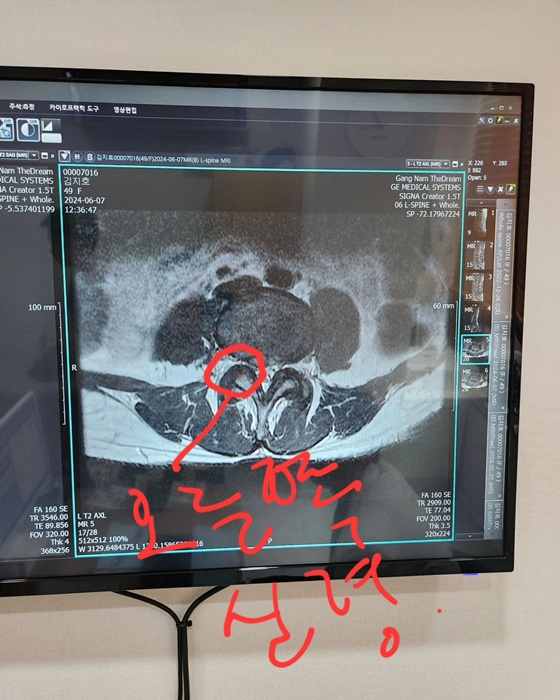

김지호는 7일 자신의 인스타그램에 척추 엑스레이 사진을 공개하며 "당분간 모든 걸 내려놓고 쉼에 들어간다"라고 활동 중단을 선언했다.

그는 "허리 디스크가 안 좋아진 걸 알고 있었음에도 인정하고 싶지 않은 마음에 '근육일 거야, 인대 통증일 거야' 계속 다른 곳에서 이유를 찾았다. 디스크라면 꼼짝없이 쉬어야 하니까. 근데 오른쪽 중둔근(중간볼기근) 통증이 허벅지를 타고 종아리까지 가더니 발바닥까지 마비된 듯 뜨겁고 저리기 시작했다"라고 터놓았다.

이어 "자전거를 타고 하누만아사나를 하고 사마코나를 하고 둔부와 햄스트링이 경직돼 아픈 줄 알고 계속 요가를 했는데 결국 더 악화시키는 방향으로 나를 몰아가고 있었던 거다. 두려웠다. 이제껏 했던 나의 시간과 노력이 사라질까 봐. 그리고 요가를 하며 집중하고 땀 흘리는 시간이 사라질까 봐. 하지만 나의 무식함과 어리석음이 더 안 좋은 결과를 초래했고 이번에 정말로 3주 정도 아무것도 안 하고 가능하면 누워있기로 했다. 앉아 있는 것도 안 좋다 하시니 할 수 없지"라고 전했다.